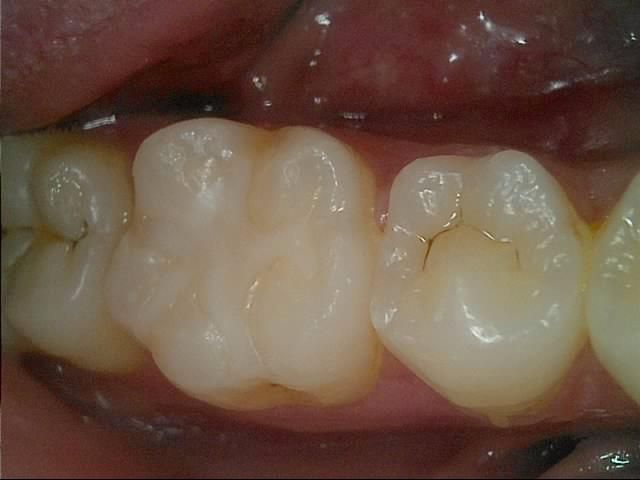

사진속 충치가 다시 번지면 인레이인가요?

사진속 구강상태에서 초기 정지우식이라고합니다. 근데 재광화가풀려 며칠동안 조금이라도 정지우식이 다시 진행되었다면, 진행된지 고작 2주정도 지났다고 쳐도 인레이가 필요한치아가 있나요? 많이 진행되지않고 2주동안 이제막 충치가번지기 시작하는경우, 레진인지 인레이인지 궁금합니다

이정도면 초기상태 충치가 맞고 여기서 좀 더 진행되더라도 인레이까지는 안갈 것 같습니다.

충치가 진행이 되는 것이 치아 사이의 경우에는 보통 레진보다는 인레이로 치료하는 것이 일반적입니다.